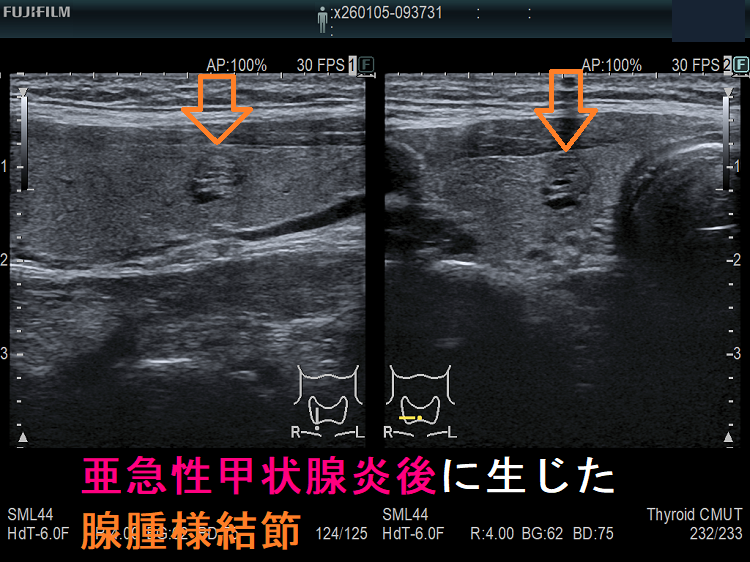

上記のようにならなくても、亜急性甲状腺炎で甲状腺組織が破壊され、さらに代償的の組織増殖が起こると、

- のう胞変性(嚢胞変性);甲状腺組織が溶けてしまい、空洞ができる

- 代償的に組織が増殖し、腺腫様結節(過形成結節)→腺腫様甲状腺腫

が生じます。長崎甲状腺クリニック(大阪)では、亜急性甲状腺炎が終息して数カ月後に、さらには年単位で甲状腺超音波(エコー)検査を施行しています。

亜急性甲状腺炎治癒後;矢印が腺腫様結節